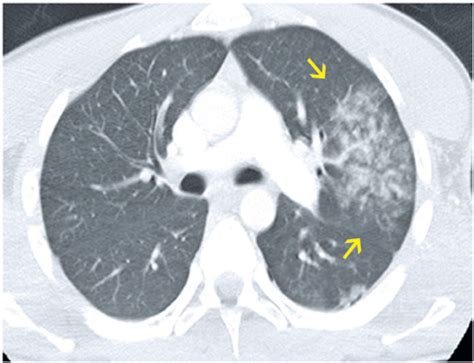

Receiving a radiology report that mentions ground glass opacity in lungs can be an unsettling experience. When a doctor or radiologist uses this term, it refers to a specific appearance on a CT scan—a hazy, gray area within the lungs where the lung tissue appears denser than normal but is not fully solidified. Unlike dense nodules or solid masses, ground glass opacities (GGOs) are characterized by this "foggy" quality, which allows underlying blood vessels and bronchial structures to remain partially visible on the imaging. Understanding what this finding means is the first step in navigating your respiratory health, as it is not a diagnosis in itself, but rather a descriptive sign that requires further investigation by your medical team.

At its core, a ground glass opacity in lungs represents a partial filling of the air spaces (alveoli) in the lungs or a thickening of the interstitium (the framework of the lungs). While normal lung tissue is mostly air and appears black on a CT scan, GGOs look like a light cloud or a blurred, frosted glass pane. This phenomenon occurs because the density of the lung has increased slightly, but the air is not completely replaced by solid material, such as fluid, pus, blood, or fibrous tissue.